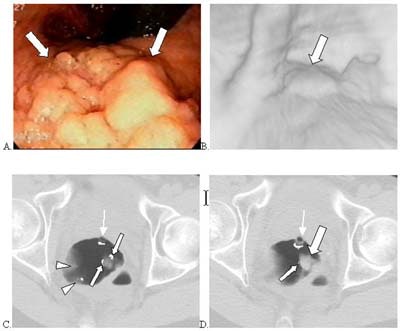

![]() |

| Above, images from a previous patient series. 3.5-cm villous adenoma (large arrows indicate soft tissue mass; small arrows, automated detection mark) in the rectum of 54-year-old male detected by computer program but not by either radiologist. (A) Conventional colonoscopy. (B) Perspective CTC endoluminal view. (C, D) Axial supine CTC images on two adjacent sections. In (D), automated detection mark (small white line on edge of mass) appears small but was larger on adjacent section over top of polyp (C). Tip of rectal tube (thin arrows) and false positives on rectal folds also marked by computer algorithm (small arrowheads). Summers RM, Jerebko A, Franaszek M, Malley JD, Johnson CD. Colonic Polyps: Complementary Role Of Computer-Aided Detection in CT Colonography. Radiology 225: 391-399 (2002). Reproduced by permission of RSNA. |

For example, CAD alone found a 2-cm tubular adenoma in the cecum, and an unusually shaped 3.5-cm villous adenoma in the rectum.